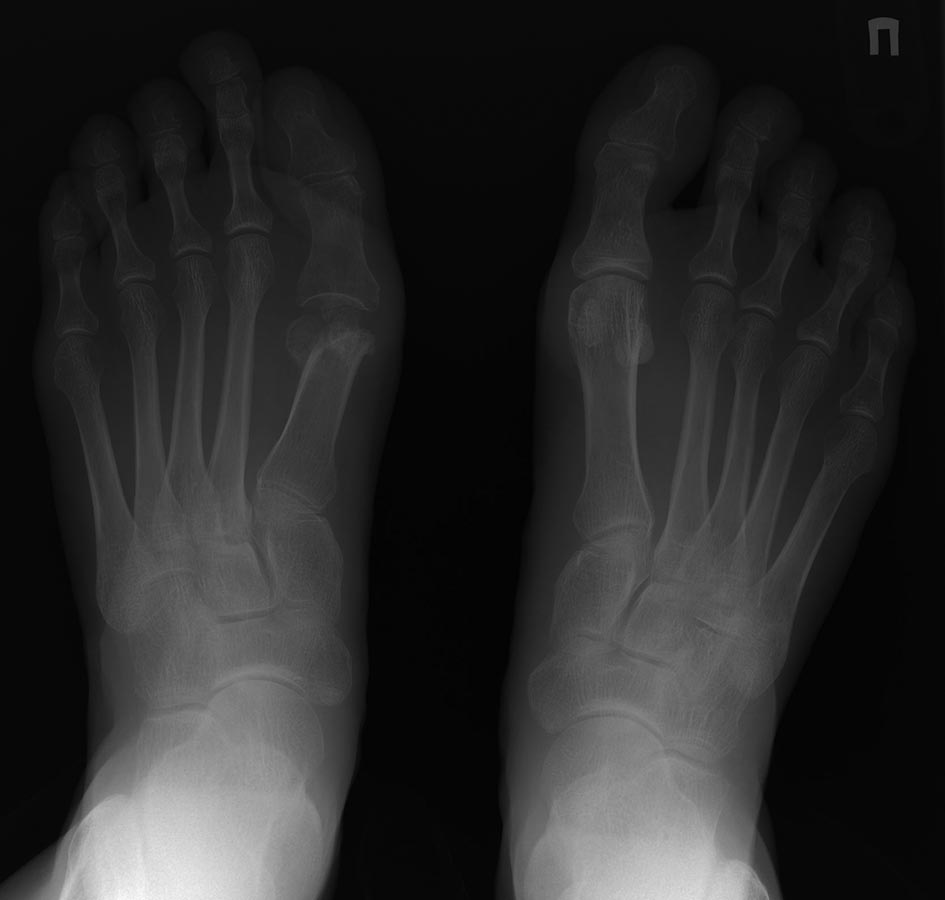

Помогите определиться с тактикой лечения. Пациентка 54 года. Жалобы на

боли в области 1-го плюснефалангового сустава и под головками 2-й и 3-й

плюсневых костей при осевой опоре. Из анамнеза: в 2015 году в ЦРБ в

проекции головки 1-й плюсневой кости было хирургической вмешательство с

целью лечения вальгусной деформации 1-го пальца. У кого какие мысли по

этому случаю и какова тактика лечения.